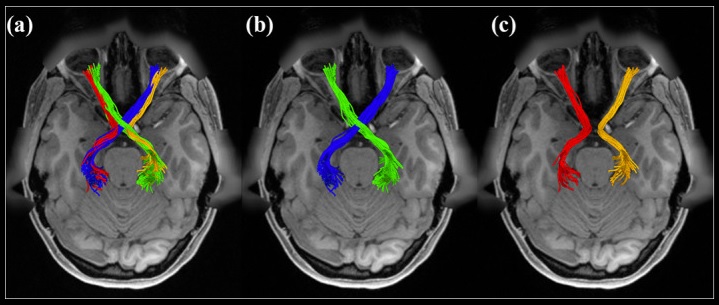

The development of the retino-geniculate system has been modeled by Markowitz et al 2012. In its final form the retino-geniculate pathway is shown below, as visualized by MRI diffusion tractography.

(figure from J He et al 2021)